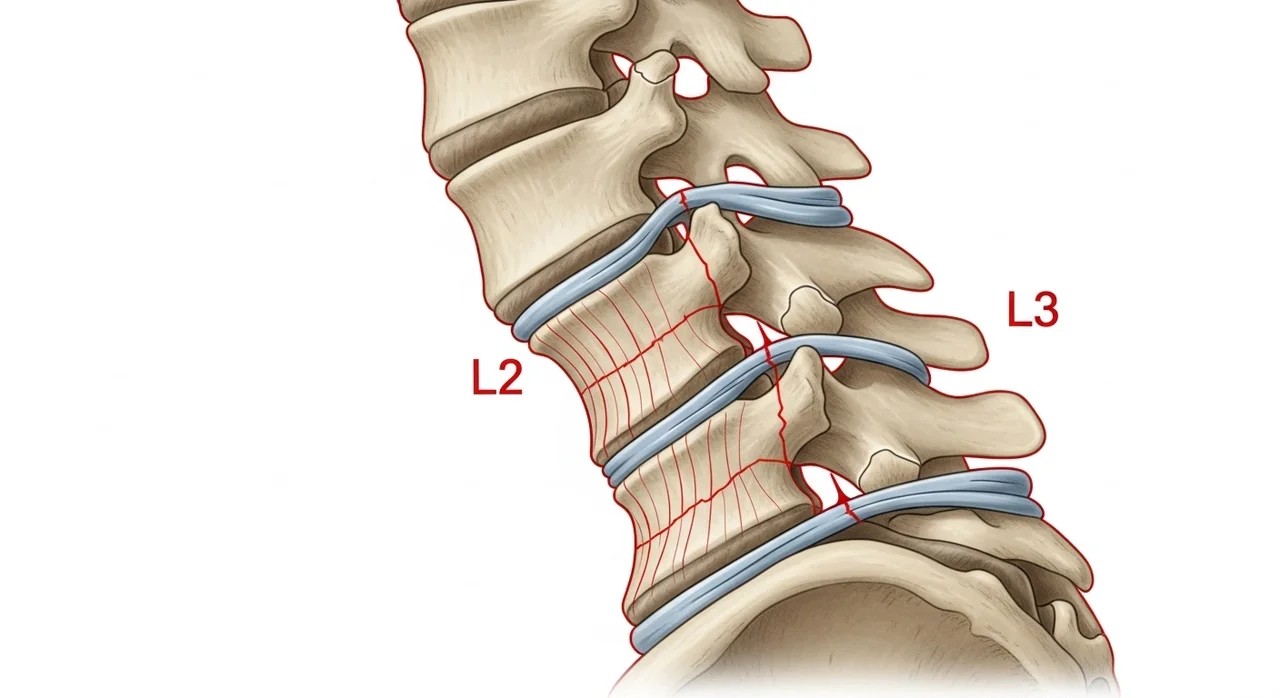

소리 없이 찾아오는 척추 압박 골절의 공포

척추 골절은 고관절과 달리 특별한 사고 없이도 발생할 수 있습니다. 무거운 물건을 들거나, 심지어 심한 기침을 하다가 척추뼈가 주저앉는 '압박 골절'이 나타나기도 해요.

"골다공증 환자의 약 50%는 평생 한 번 이상의 척추 골절을 경험하지만, 통증이 적어 모르고 지나치는 경우가 많습니다."

만약 예전보다 키가 3cm 이상 줄었거나, 등이 점점 굽어간다면 이미 척추 골절이 진행 중일 수 있습니다. 척추가 무너지면 내부 장기가 압박을 받아 소화 불량이나 호흡 곤란이 올 수도 있으니 꼭 검진이 필요해요.